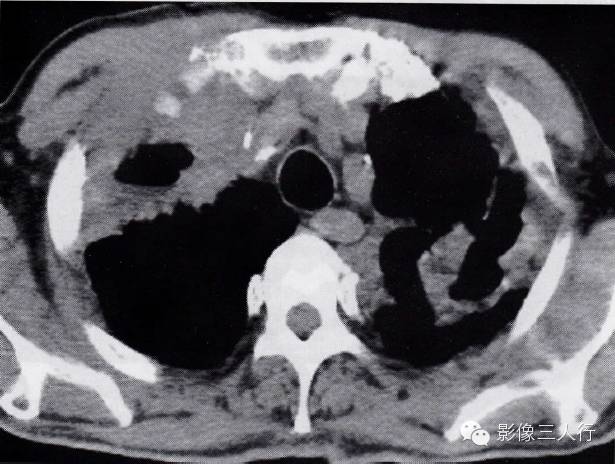

肺结核合并肺癌的CT表现及鉴别诊断

图2-95肺结核合并肺癌

双肺上叶见肺结核空洞形成,右肺上叶还有包块影,紧贴前胸壁软组织肿胀,并有肋骨前端骨质破坏。肺穿刺为肺鳞癌